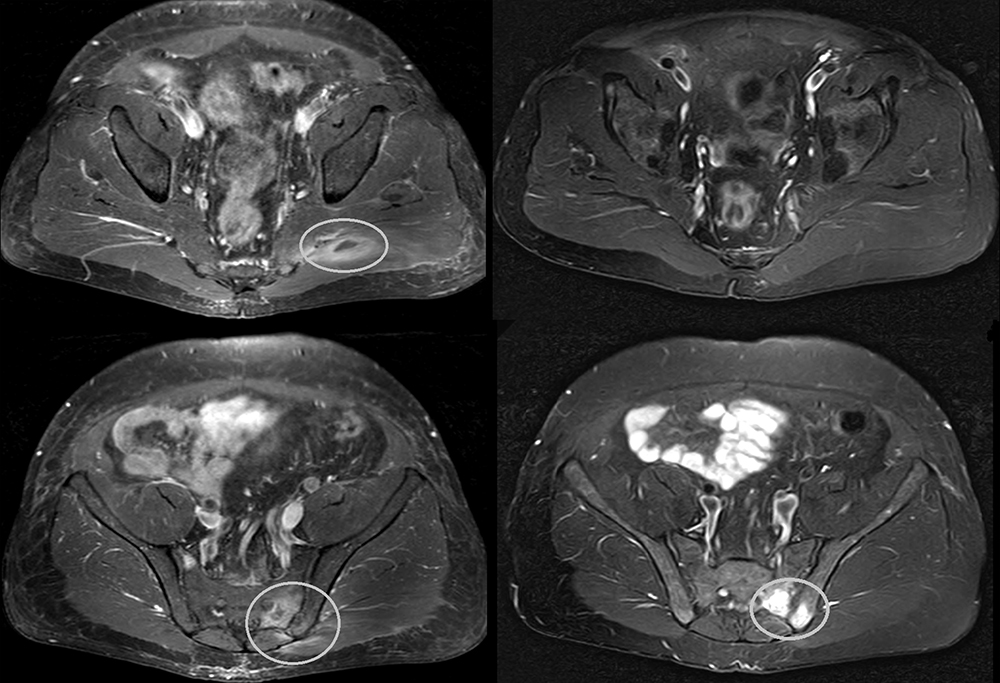

Se presenta el caso de una mujer de 40 años de edad que consultó por una historia de 7 años de evolución de dolor generalizado y cansancio crónico. Había sido diagnosticada de fibromialgia por varios reumatólogos y reunía los criterios de clasificación de fibromialgia de 1990 del Colegio Americano de Reumatología. También reunía criterios de síndrome de fatiga crónica. Tenía problemas de concentración y de memoria, «foggy mind», y diarrea intermitente. La severidad de la afectación le condicionaba una vida prácticamente limitada a estar en cama a pesar de haber consultado con especialistas en reumatología, gastroenterología y también medicina natural y homeopatía. Además de los síntomas típicos de fibromialgia, fatiga crónica y diarrea intermitente, tenía aftas orales, hipotiroidismo autoinmune e historia de ferropenia. Se habían realizado múltiples estudios con resultado normal, incluyendo anticuerpos anti-transglutaminasa IgA para descartar la enfermedad celíaca.